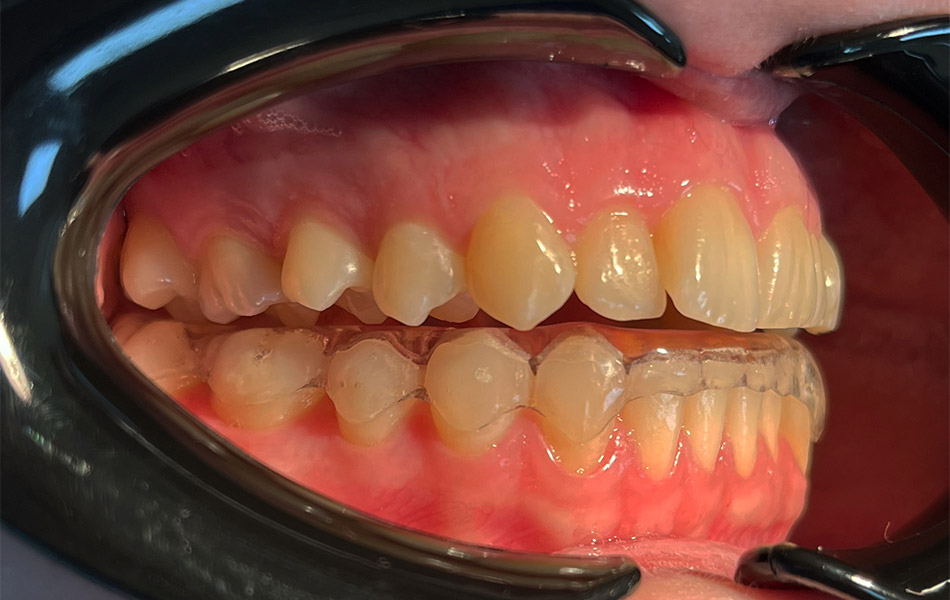

- Ограничение подвижности челюсти — специальные шины или сплинты для расслабления мышц;